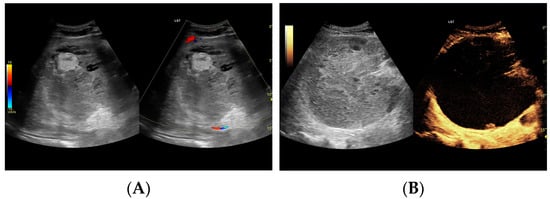

Utility of Contrast-Enhanced Ultrasound in Optimizing Hepatic Abscess Treatment and Monitoring

3. Results

3.2.1. Arterial Phase

3.2.2. Early Venous Phase

3.2.3. Late Venous Phase